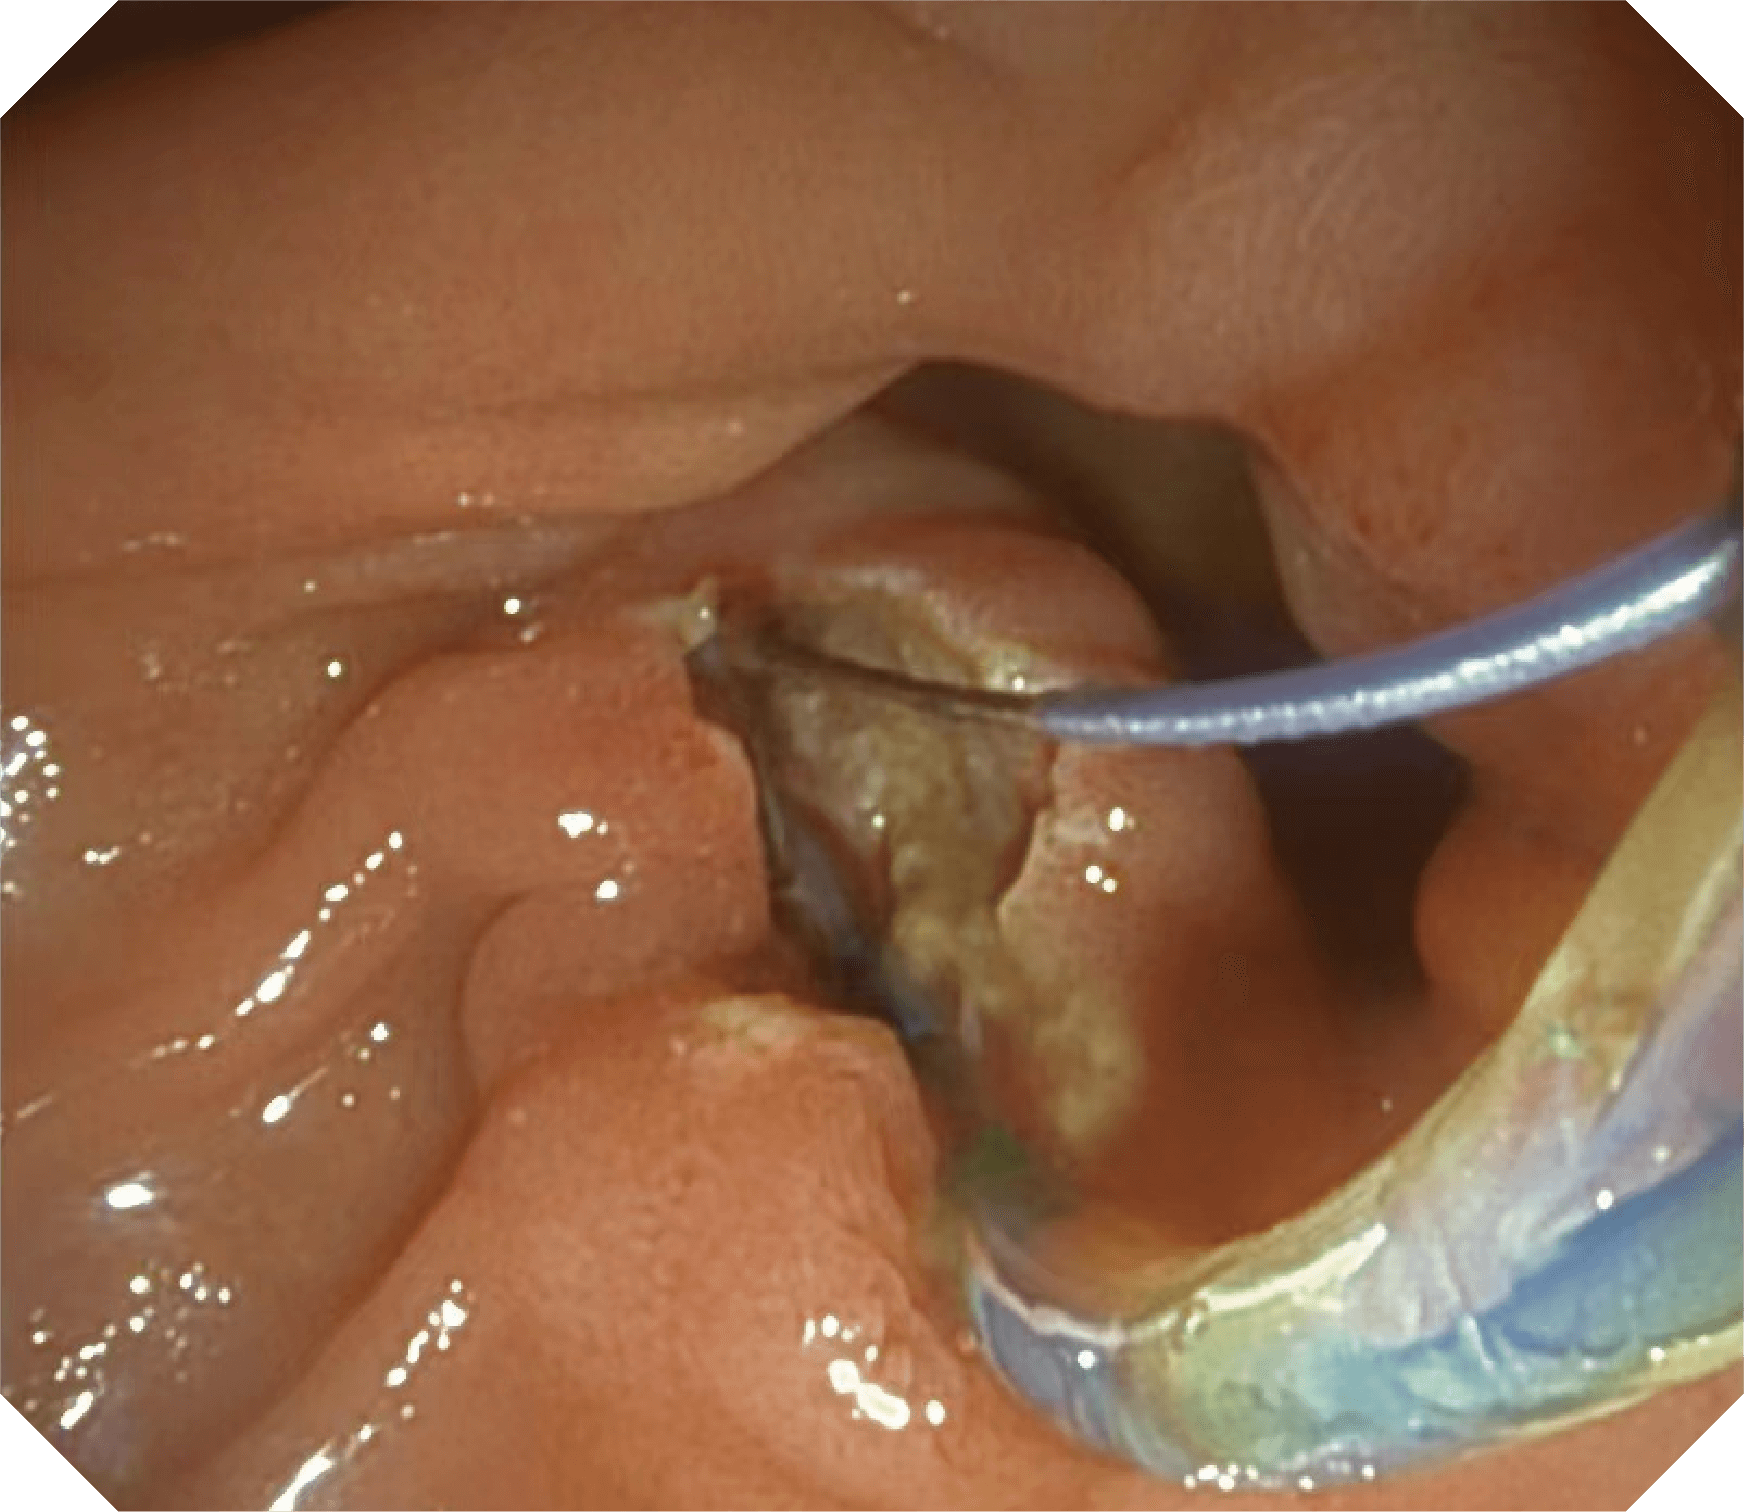

4.2mm大钳道,器械交换更顺畅

导丝机械锁紧功能

V槽设计提升导丝控制